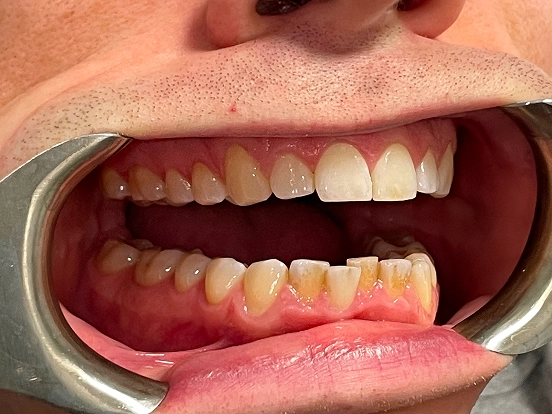

Invisalign DT

DT’s transformation with Invisalign is a perfect example of how advanced orthodontic technology can deliver incredible results. The clear aligners gradually corrected the alignment and bite issues, creating a straighter, healthier, and more attractive smile—all without noticeable brackets or wires.